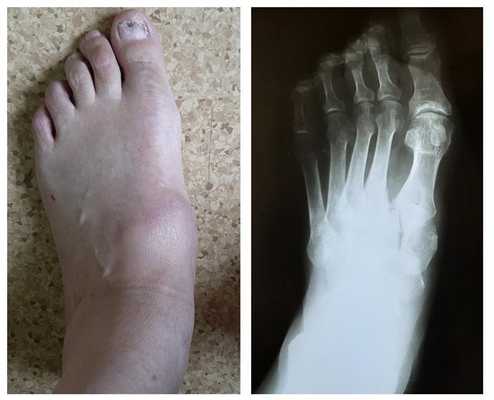

На данной рентгенограмме представлено очень серьезное повреждение стопы, возникшее следствие высокоэнергетической травмы. Результатом травмы стал вывих в суставах среднего отдела стопы).

Рентгенограмма стопы после лечения

Симптомами повреждения сустава Лисфранка являются боль в области переднего и среднего отделов стопы, усиливающаяся при осевой нагрузке. При осмотре определяется кровоподтёк, чаще по подошвенной поверхности, в проекции сустава Лисфранка.

При значительном смещении может быть заметна грубая деформация. Отёк диффузно распространяется по всей стопе. Боль при пальпации в проекции связки Лисфранка.

Пациенты с переломо-вывихами в суставе Лисфранка часто оказываются в ситуации, когда никто из врачей не хочет за них браться. Так случилось и с пациентом Ж. 64 лет, который получил травму ещё в 2001 году, но оперировать его отказались. Боль и деформация прогрессировали, и на протяжении последних 10 лет пациент уже не мог пройти больше 800 метров. Постоянное ношение ортопедических стелек не давало облегчения симптомов.

После осмотра в отделении ортопедии №2 ГКБ №13 принято решение о проведении операции – открытому устранению вывиха, артродезе 1-2-3 плюсне-клиновидных суставов, 1 межклиновидного сустава при помощи винтов и пластины, трансартикулярной фиксации спицами 4-5 плюсне-клиновидных суставов.